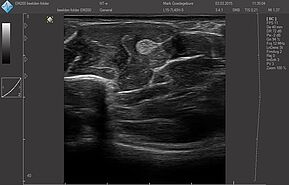

- Костно-мышечная система

Датчики имеют большую чувствительность и высокое разрешение, благодаря чему обеспечивают максимальное проникновение и улучшают соотношение сигнал /шум. В результате формируется максимально четкая детализированная картинка УЗИ изображения.